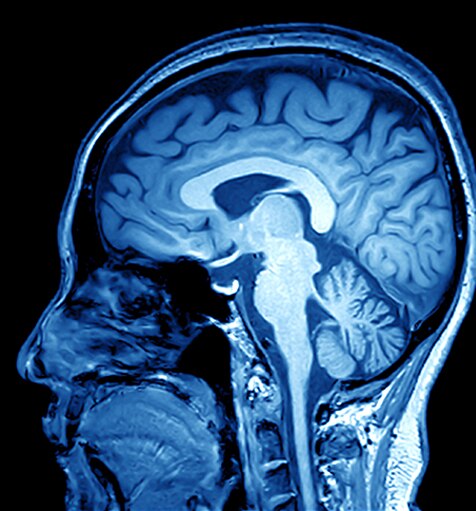

L’IRM (imagerie par résonance magnétique) est une technologie d’imagerie non invasive qui produit des images en coupe du corps. Elle est utilisée dans de nombreuses applications médicales, notamment : imagerie musculo-squelettique, gastro-intestinale, oncologique, cardiovasculaire et neurologique. L’IRM peut différencier les structures des tissus mous sur tous les plans, ce qui en fait un outil de diagnostic précieux.

Les scanners IRM génèrent un champ magnétique fort qui, combiné à des courants de radiofréquence, stimule des molécules spécifiques dans le corps.

Le comportement de ces molécules permet de générer une image en trois dimensions des tissus corporels. Voici quelques exemples d’images obtenus par IRM :